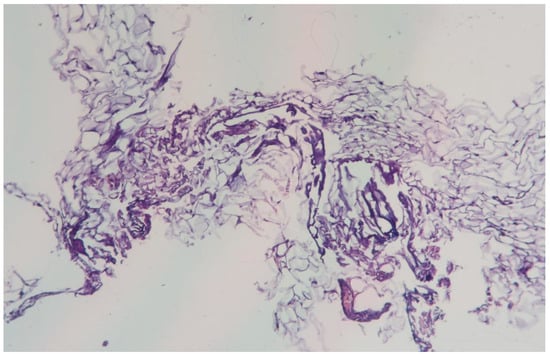

3.1.9. Clinical Case 9: Adipose Tissue Dissection Area, 20 W (See Figure 10)

Description: Compared to 15 W, the zone of coagulative necrosis was less pronounced.

Figure 10.

Changes in subcutaneous adipose tissue following exposure to the thulium laser at 20 W, 100 Hz. H&E staining, 10× objective magnification.